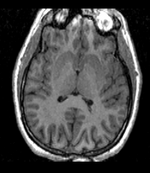

Input

|

|

|

| Target Brain | Probabilistic Atlas |

This is an example of sparse atlas co-registration. Not all atlases have an associated reference image that can be used for registration. Because the atlas represents a map of a particular tissue class probability, its contrast differs significantly from the target image.

- fixed : T1w axial, 0.9375 x 0.9375 x 1.5 mm axial, 256 x 256 x 124

- moving: Probabilistic Tissue atlas, 0.9375 x 0.9375 x 1.5 mm axial, 256 x 256 x 124

Registration Results